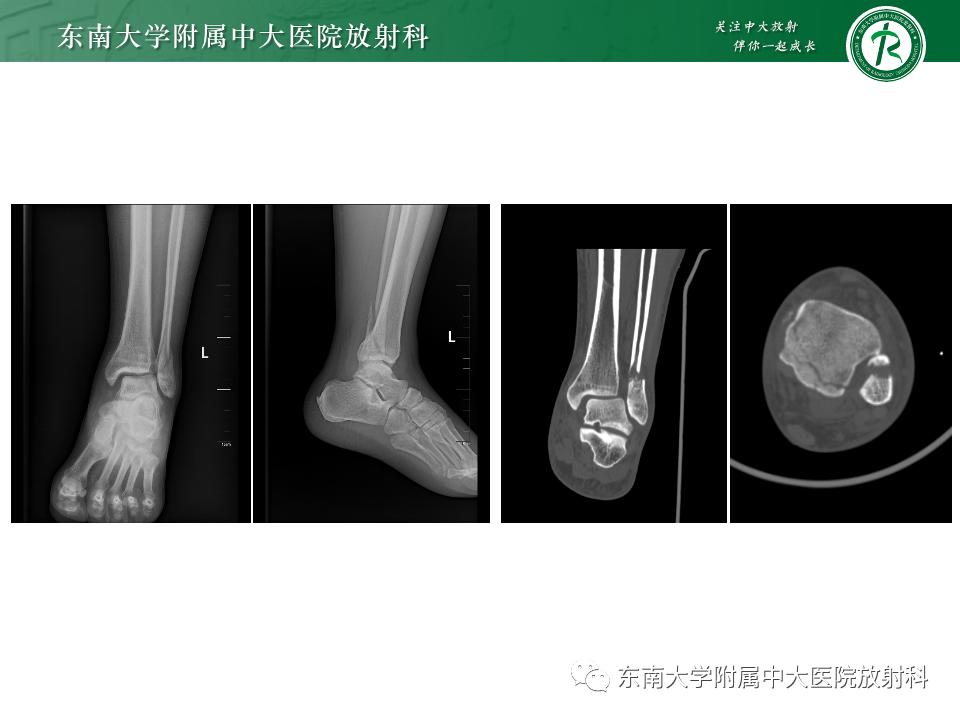

病例

• 男,39岁

• 主诉:右踝部肿痛伴活动受限 10 小时余。

• 现病史:患者 10 小时前下楼梯踩空致右踝部疼痛伴活动受限,疼痛为胀痛,运动后疼痛加剧。各足趾活动可。

影像学表现

左腓骨下段骨折伴下胫腓联合分离,好文分享深度揭秘